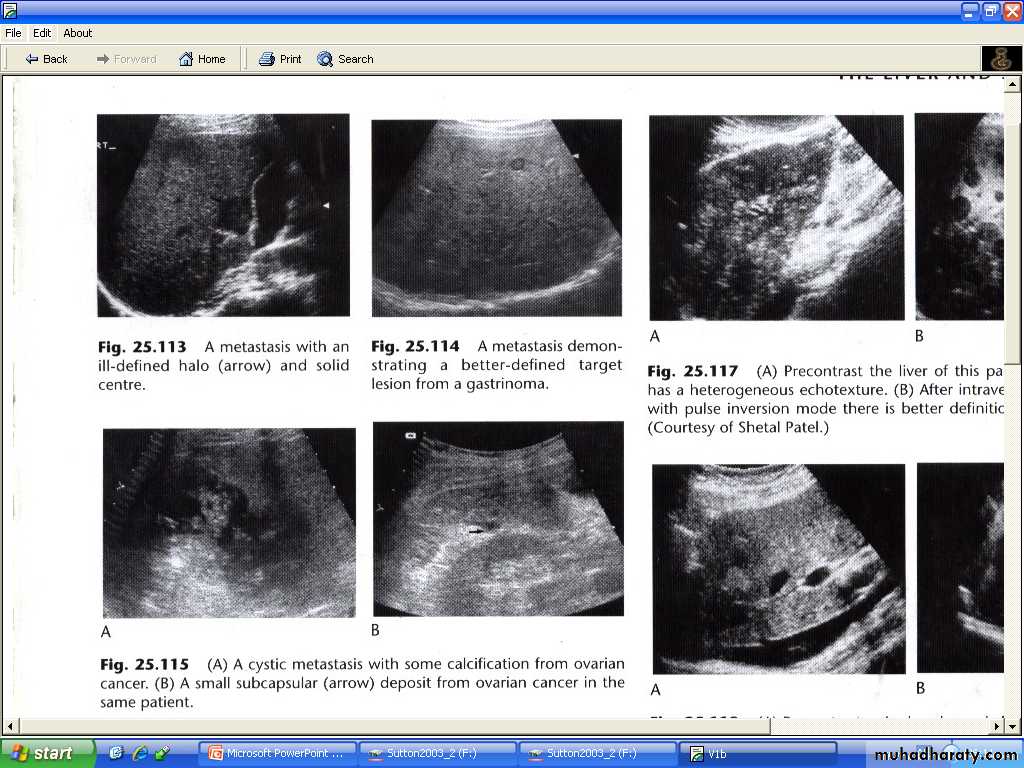

Often multiple , peripherally situated and variable sizes.

US

# may shows increase attenuation ( increase echogencity ) (echognic ) (hyperechoic ).

# more usually shows decrease echogencity ( hypoechoic ).

# At time , they show a complex echo pattern.

# When undergoes central necrosis they may even resemble cysts.

# may have an echogenic center giving an appearance described as a target lesion.

# some isoechoic to surrounding liver parenchyma ( i.e cannot be visualized sonographically )